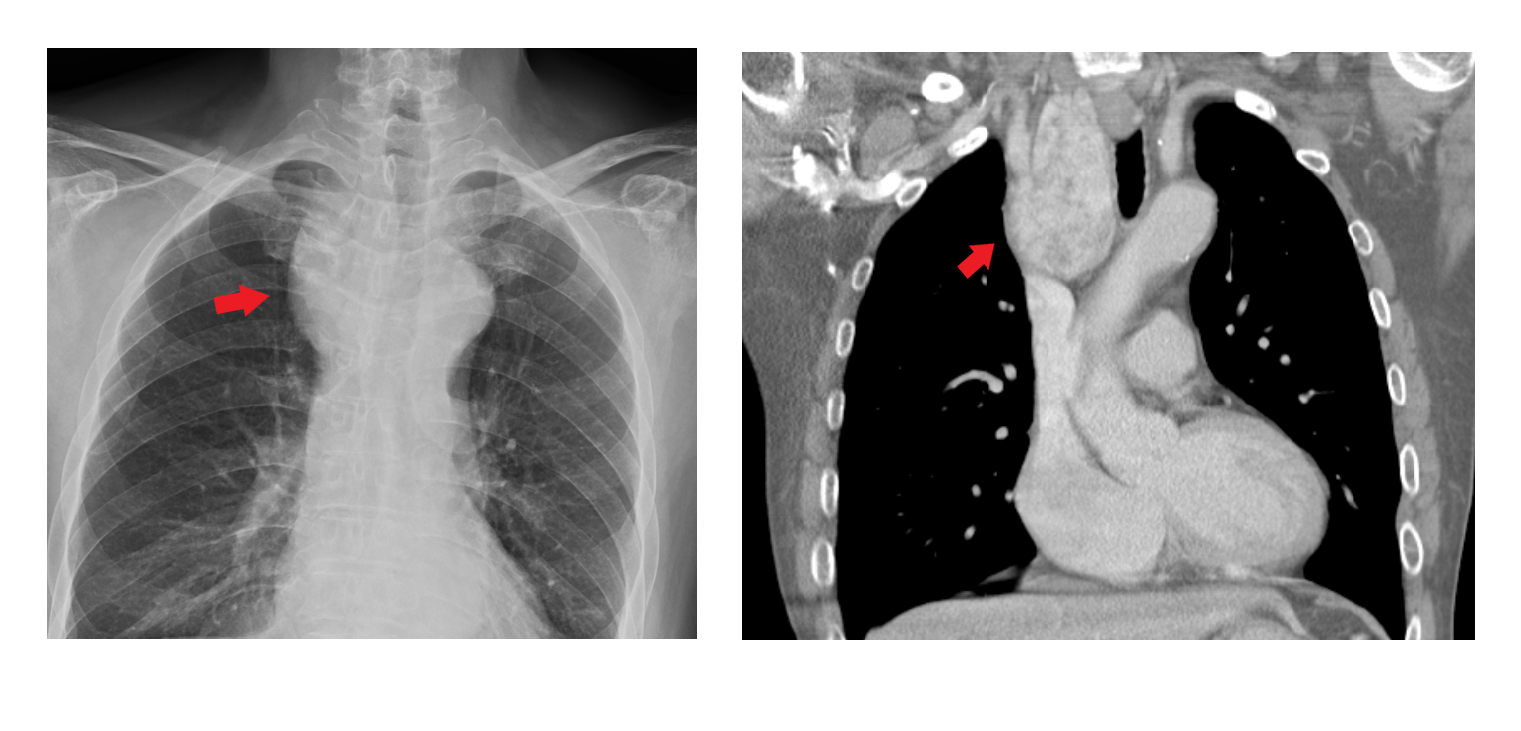

一位年約60歲的男性長期有胸悶與呼吸不順的困擾,平躺時更感覺「吸不到空氣」,就醫後透過胸部X光檢查發現氣管右側有疑似腫塊陰影,並造成局部氣管偏移中線。進一步電腦斷層掃描發現一顆由甲狀腺右葉一路延伸進入到胸腔內,約為9×5公分如鵝蛋般大小的腫大結節,已明顯壓迫氣管,建議手術切除。原被評估需切開胸骨才能切除,但患者擔憂術後疼痛影響生活,經親友介紹轉診至聯新國際醫院甲狀腺外科醫師林晏甥門診,後續僅透過前頸部切口就將腫塊完整移除,病患術後第二天即出院,目前恢復狀況良好。

林晏甥提到,針對一般良性且無壓迫症狀的甲狀腺結節,主要是以超音波與細針穿刺細胞學檢查,由於胸骨後甲狀腺結節腫大位在胸腔內難以用超音波偵測,因此常在有壓迫症狀時才被發現。常見症狀包括呼吸困難、吞咽異物感、聲音嘶啞、慢性咳嗽或喘鳴聲。他進一步提到,一旦有這些症狀,應儘早就醫檢查,可經由胸部X光及電腦斷層檢查確定診斷。對於胸骨後甲狀腺結節腫大的首選治療方式仍為手術,不僅能緩解壓迫、改善症狀,也能降低惡性變化的風險。